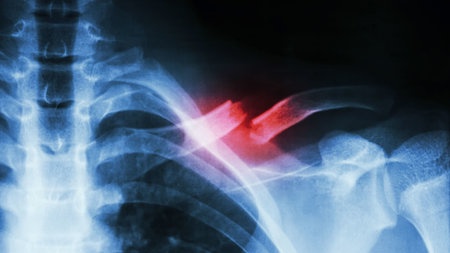

• Musculoskeletal trauma